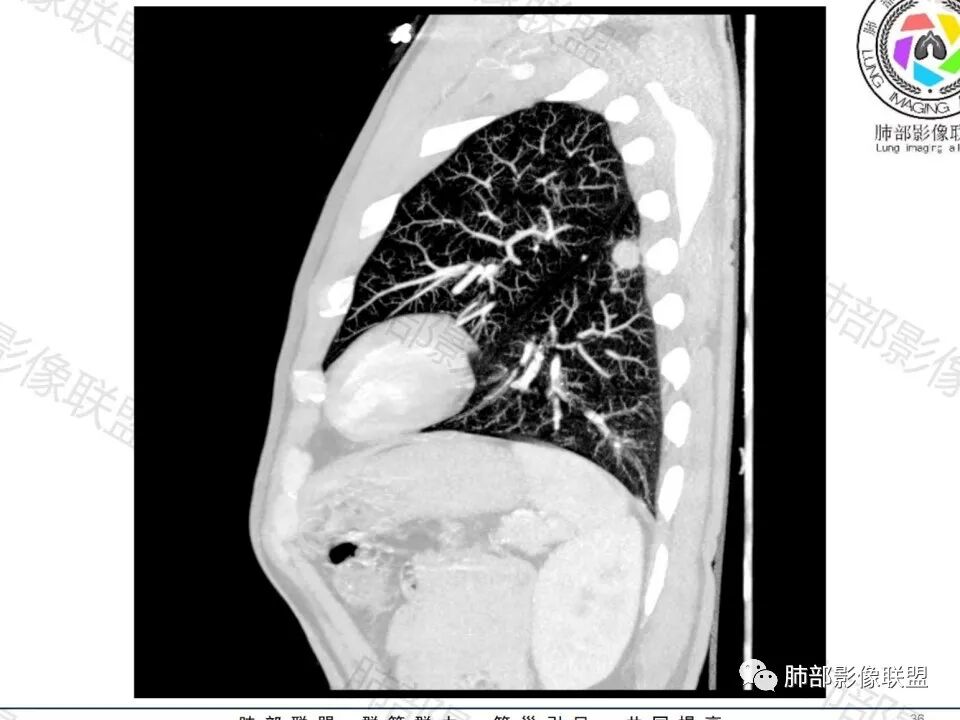

老年男性,无症状,肺气肿背景

这个囊可靠吗?

这应该是附近的肺气肿

血管进去还是比较自然

南边:

类圆形,边缘稍平直,周围晕中细微毛刺,密度均匀,均匀强化,血管走形自然,稍牵拉扭曲,支气管在近端堵塞

多发类似结节

常规思路:

1、炎性结节,多发,类似,晕,隐球菌?

2、恶性:多发:转移瘤?肺癌并多发转移瘤?